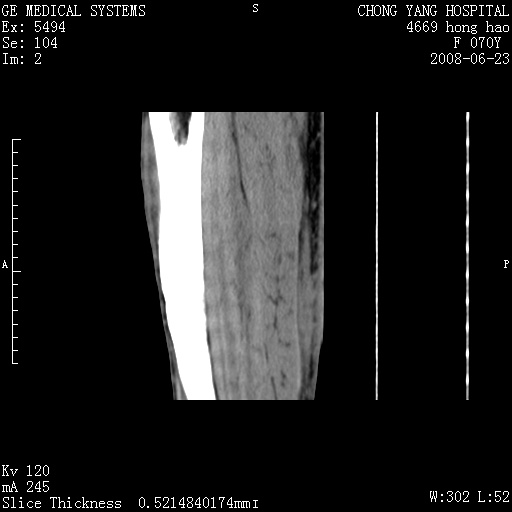

以下是引用peijunlong在2008-6-24 20:56:00的发言:[br]左小腿后方软组织皮下脂肪间隙见条片状密度增高影,范围较大,相邻皮下见条索影。[br]考虑:无菌性炎症可能性大[br]鉴别:主要与蔓状血管瘤鉴别,蔓状血管瘤也可表现为软组织内葡伏生长的扁平状的软组织密度影,但它的范围更大,且主要在软组织内,肌间隙中,皮下脂肪间隙内罕见。